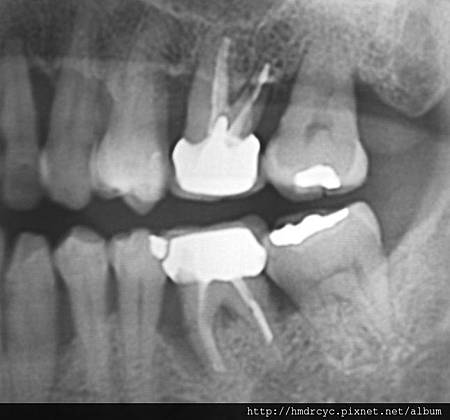

2. 牙周病與骨頭破壞

牙周病不管在假牙或自然牙齒

都必須X光來診斷嚴重程度

輕微的牙周病經過照X光片

可以檢查出牙肉底下牙結石的位置

而牙周病最可怕的部分就是造成骨頭破壞

有時候外表看起來不錯的牙齒

其實裡面骨頭以經破壞嚴重甚至造成動搖

嚴重者骨頭以經完全破壞

牙齒失去支撐 就會浮起來

這時就只能考慮拔除

在牙橋有時感覺動搖度並不大

那是因為跟其他牙齒聯結在一起的關係

單顆牙齒骨頭破壞嚴重就會馬上出現動搖

骨頭破壞後原本骨頭位置被發炎的肉取代

甚至形成膿包